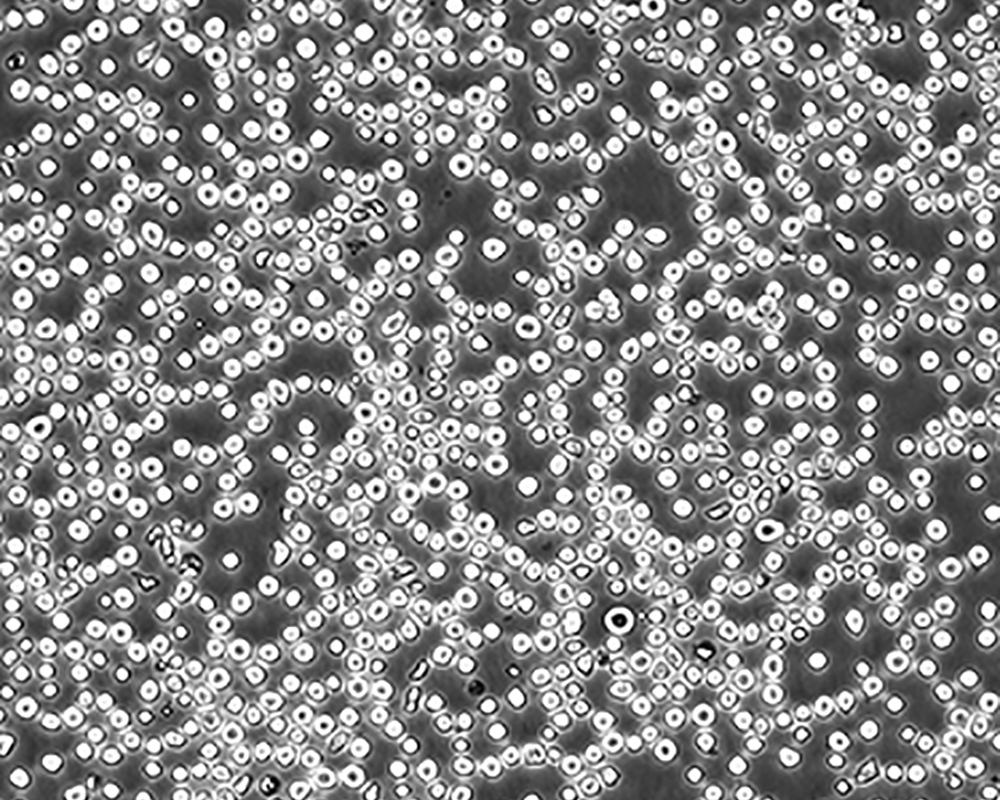

中文名稱(chēng) 人急性淋巴細(xì)胞白血病細(xì)胞

組織來(lái)源 急性T淋巴細(xì)胞白血病;女性

生長(zhǎng)特性 suspension

形態(tài)特征 lymphoblast

細(xì)胞描述 CEM/C1是人T細(xì)胞白血病細(xì)胞株CCRF-CEM(見(jiàn)ATCC CCL-119)具有喜樹(shù)堿抗性的衍生株。1991年細(xì)胞株選擇并亞克隆了對(duì)CPT的抗性。細(xì)胞表現(xiàn)出對(duì)CPT類(lèi)似物水溶性的托泊替康和非水溶性的9-氨基-CPT及10,11-亞甲二氧基-CPT具有交叉抗性。CEM/C1細(xì)胞對(duì)CPT的敏感性較母系CEM細(xì)胞低31倍。CEM/C1細(xì)胞表現(xiàn)非典型的多藥抗性和轉(zhuǎn)換拓補(bǔ)異構(gòu)酶I催化活性。對(duì)CPT的抗性維持6個(gè)月以上。